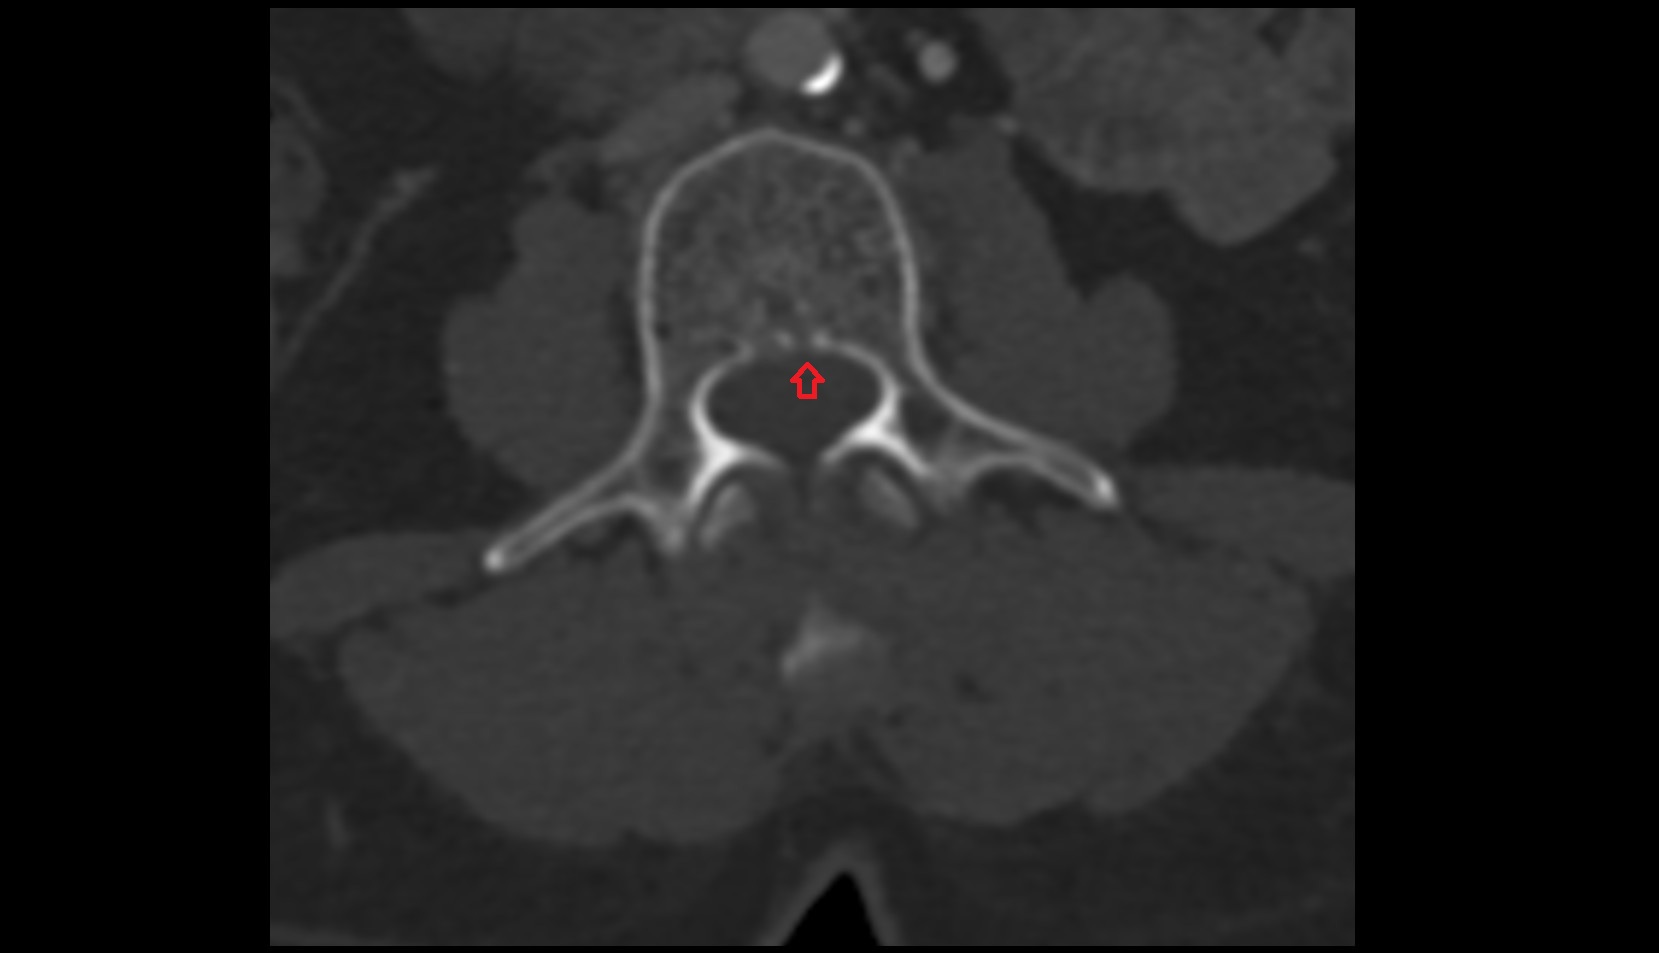

- Spinal cord

- subarachnoid space of spinal cord